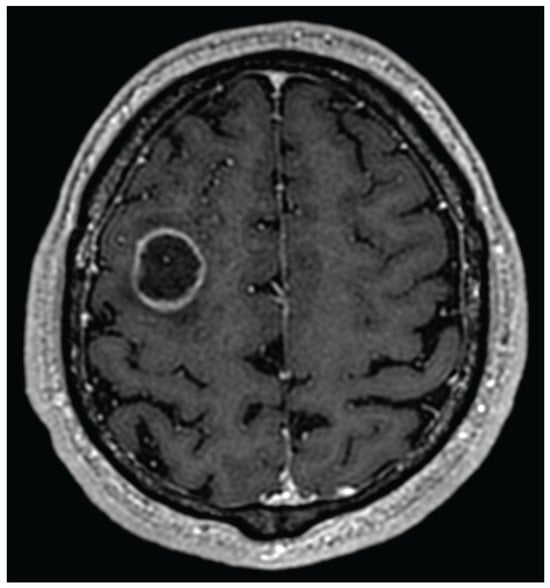

- Gaillard, F.; Sharma, R.; Le, L. Cerebral Ring Enhancing Lesions. Radiopaedia.org. 2009. Available online: https://radiopaedia.org/articles/cerebral-ring-enhancing-lesions-differential?lang=us (accessed on 24 June 2025).